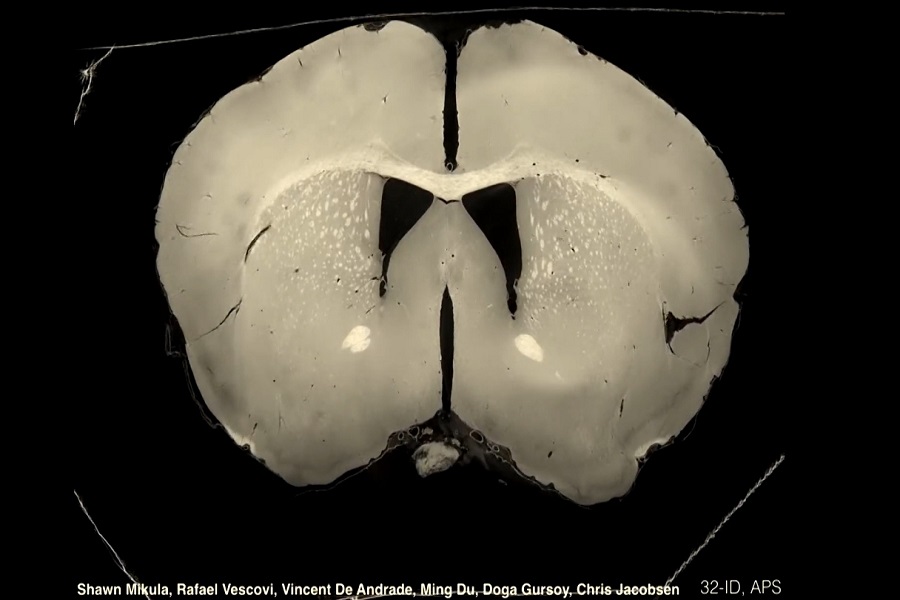

نماهایی مختلف از مغز کامل موش گرفته شده به روش میکروسیتی

طرز کار دستگاه میکروسیتی در قسمت b با چرخش نمونه از بخشهای مختلف نمونه عکسبرداری میشود. (تصویر در سال ۱۳۹۶ در مجله eNeuro چاپ شده است)